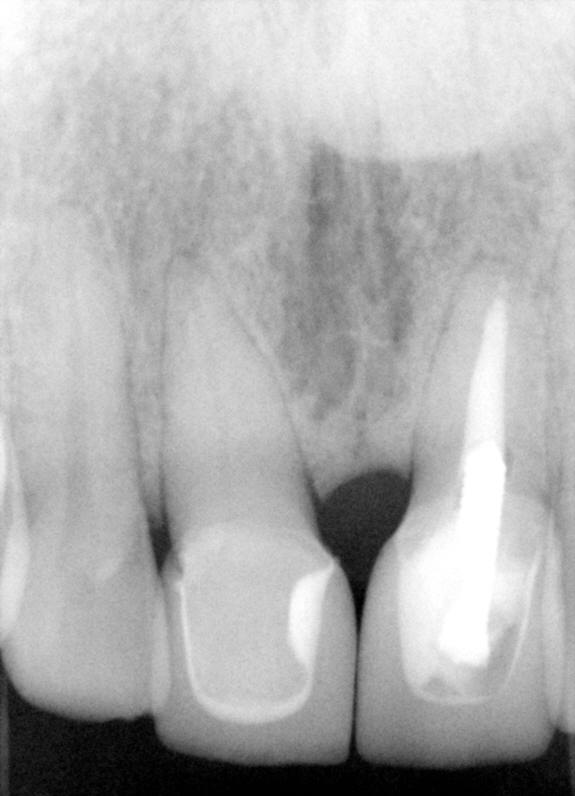

这一例我们选用陶瓷贴面修复#8牙,陶瓷牙冠修复#9牙,这是因为8号牙缺损太大些,补牙有一定困难,陶瓷贴面更漂亮,不容易变色。九号牙缺损更大,而且做过根管治疗(图二),需要牙冠保护,它不能做内漂白,是因为这颗牙齿当中有一个金属桩,后者很难去除,也就是说我们没有空间作内漂白(102期,234期,242期)。结果术后外观不错(图四),术后X-光片(图五)显示陶瓷贴面和牙冠与牙齿结合密切。 |

| 图四 | 图五 |